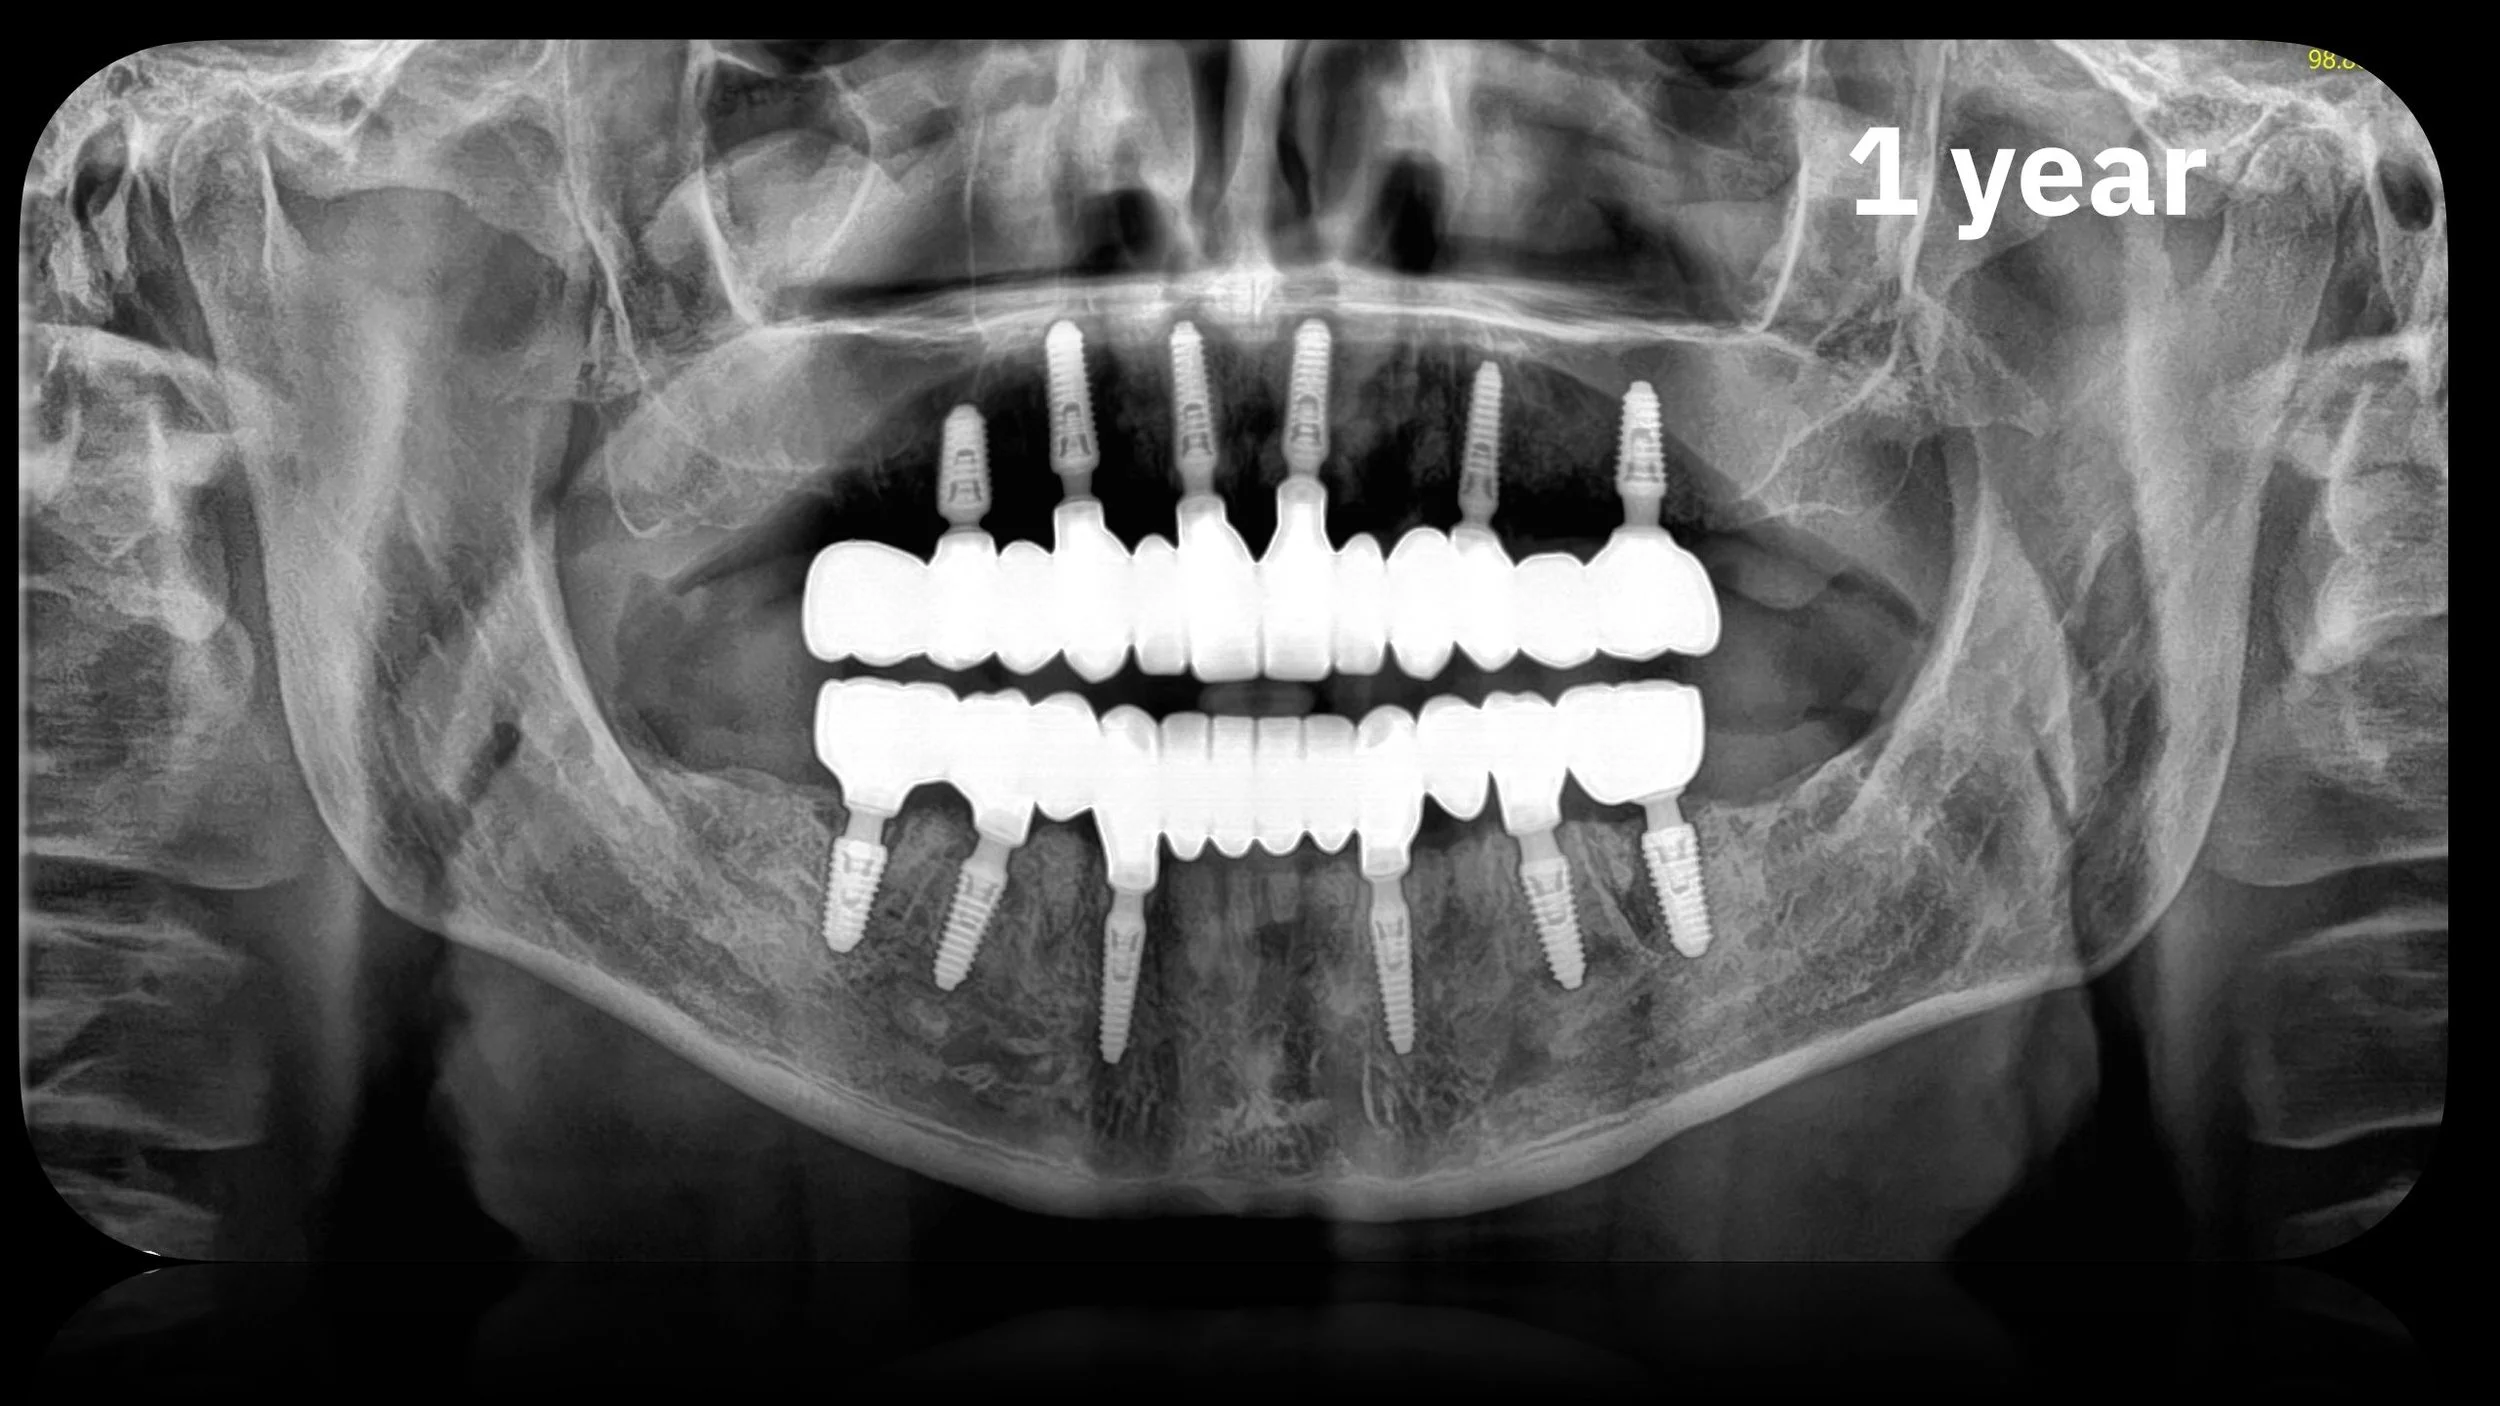

Full mouth rehabilitation can be 100% digital. From planning, to surgery, to final prosthetics.

Would you like to learn, how to do full mouth rehabilitation prosthetics without impression or photogrammetry and still achieve 100% passive fit? Just using intraoral scanner and CBCT.

1. How to achieve passive fit only with intraoral scanner + CBCT.

• How to achieve a passive fit using only an intraoral scanner and CBCT (no impression or photogrammetry)

PROOF OF CONCEPT AND USABILITY

• Up to 10 years of follow-up data with this protocol

• 300 completed cases (93% prosthetic success rate 2017-2024 on 148 arches)

Medical case using R2GATE guided surgery and AnyRidge implants